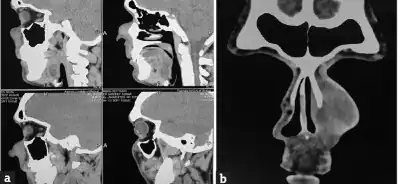

A culture of the infected tissue of the individual suspected of having Entomophthoramycosis[7]Imaging using MRI or CT scan may also be done[4]